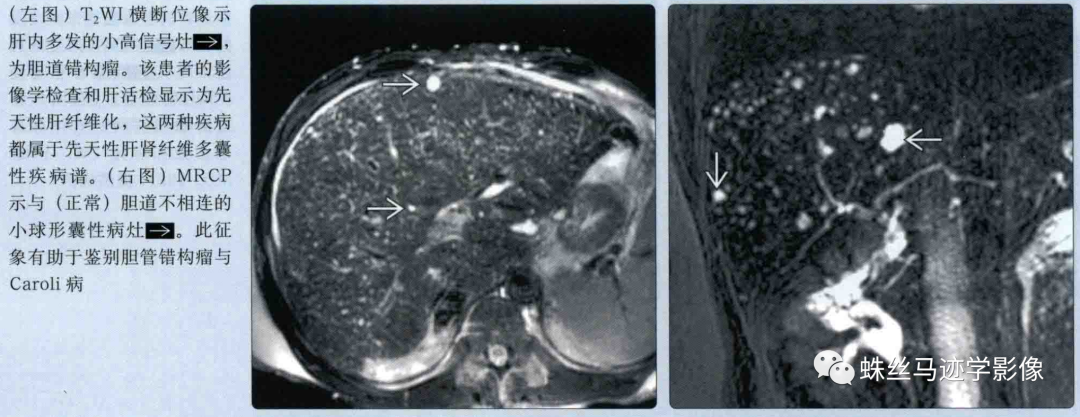

肝内胆管错构瘤和先天性肝内胆管囊状扩张症(Caroli病)-1